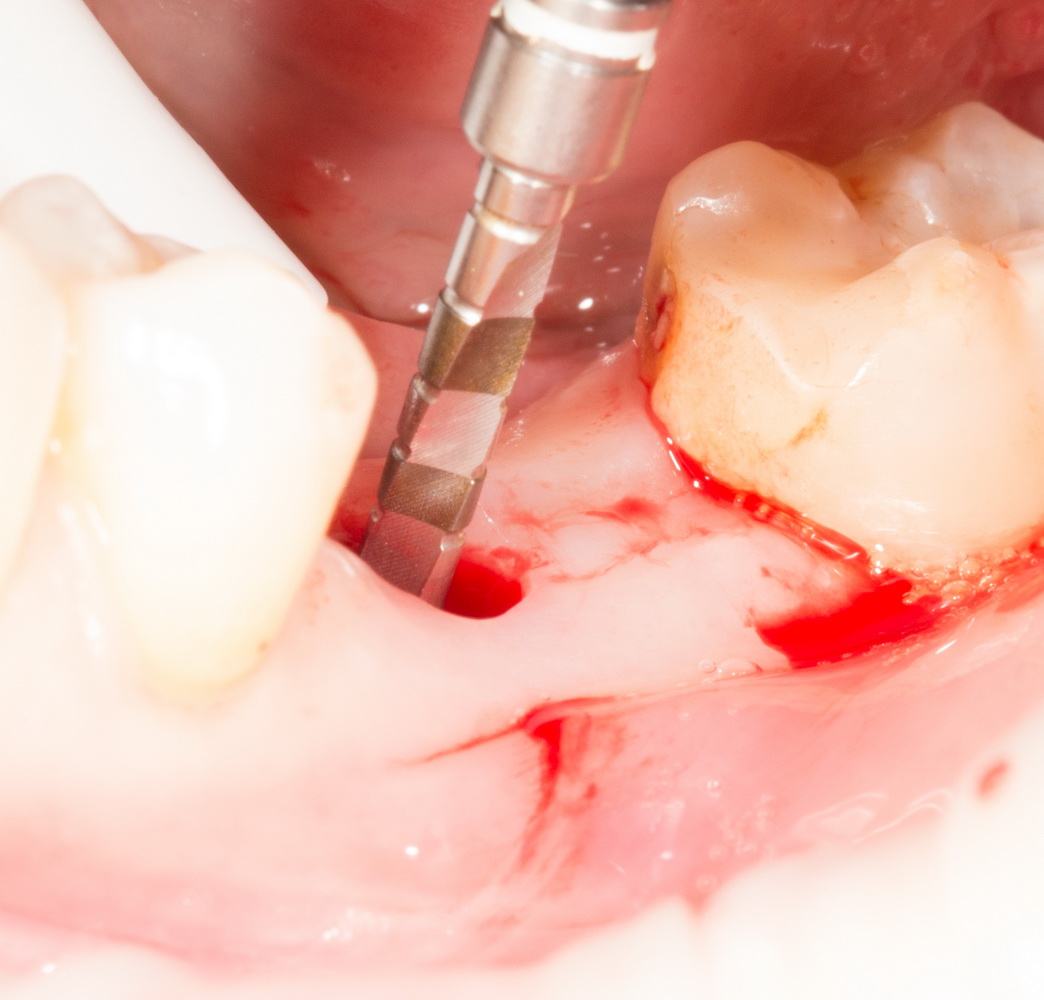

Дальнейшая подготовка лунки идет через образовавшееся отверстие:

С помощью последовательного набора фрез, лунка расширяется и углубляется под имплантат нужного диаметра. Тут важно знать толщину слизистой оболочки (измеряется зондом в самом начале) и делать поправку по глубине. Скажем, нужно поставить имплантат длиной 11 мм, толщина десны по пародонтологическому зонду — 3 мм. Следовательно, фреза погружается до отметки 14-15 мм.

Контроль глубины в данном случае затруднен и поэтому очень важен. За исключением некоторых видов трансгингивальных и субкрестальных имплантов, наш «корень зуба» должен оказаться на определенной глубине, его полированная фаска и ортопедический интерфейс должны быть выше уровня десны. Если при обычном линейном разрезе мы видим костную ткань и это облегчает ориентирование по глубине, то в данном случае ориентиров почти нет.